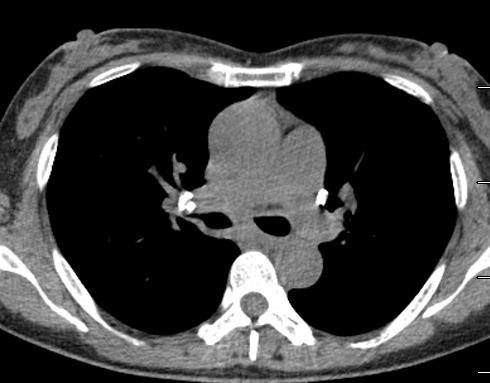

图10~图15 胸部CT示双肺多发钙化灶

问题出在哪儿?

右中间支气管的钙化病灶向外移动,钙化病灶的尖端刺激到支气管粘膜了(图16)。

图16 胸部CT